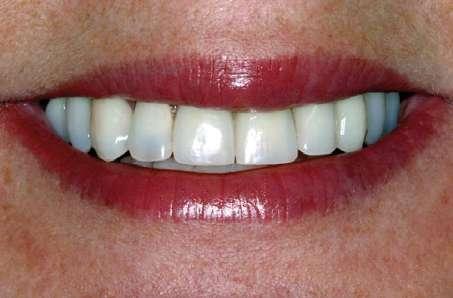

Figuras 23-25. Imágenes de la paciente en el seguimiento a los 23 años. Vemos la expresión facial, la estética de la sonrisa y el soporte labial que permanece inalterable con el paso del tiempo.

La paciente V.P., de 58 años, acude a nuestra consulta por una disminución de su capacidad masticatoria. Además, solicita una mejora de la estética de su sonrisa y de su rostro, afirmando que no está satisfecha con el color y la apariencia de sus dientes que, incluso en las expresiones faciales más pronunciadas, son poco evidentes y presentan planos inclinados poco naturales.

El historial clínico no revela ninguna patología incompatible con el tratamiento odontológico y, en particular, con el tratamiento implantológico, y presenta un buen estado general de salud: la paciente se puede clasificar como ASA1. El examen objetivo del rostro muestra una reducción de la dimensión vertical con un ensanchamiento de los pliegues nasolabiales y una pérdida de tono de los tejidos blandos periorales, con un empeoramiento general de todos los parámetros estéticos (Fig. 1). Durante el examen clínico intraoral se observa en el maxilar una prótesis fija de cerámica con soporte dental, mientras que en el arco inferior está presente la dentición residual del paciente con espacios edéntulos intercalados (Fig. 2).